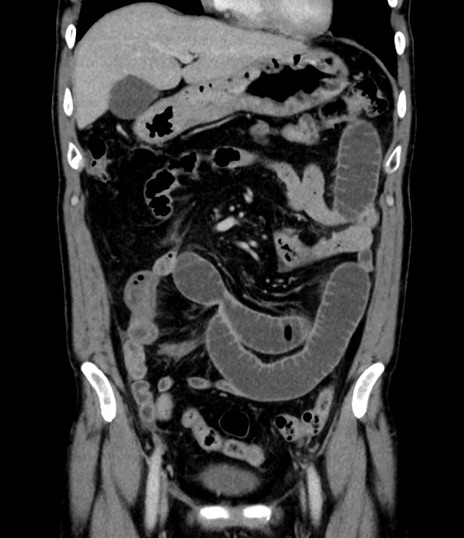

症例8(冠状断像)

【症例】 60歳代男性

【主訴】 黒色吐物

【現病歴】 4日前から嘔気自覚、2日前の朝食後にも嘔気あり、自分で手で嘔吐反射起こし嘔吐したところ血が混ざっていたため受診。

【既往歴】 5年前汎発性腹膜炎を伴う急性虫垂炎で手術、高血圧、前立腺肥大症、高脂血症

【身体所見】 腹部正中に手術癩痕あり 腹部平坦・軟圧痛なし膨満感あり

【データ】WBC 8400、CRP 4.54